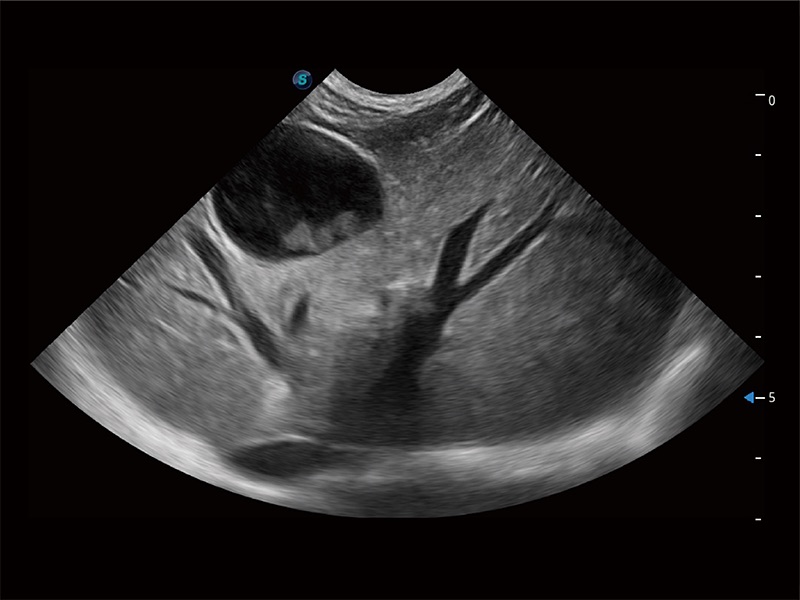

(犬)肝脏

(犬)胎儿主动脉弓立体血流

(犬)肠道

(犬)胎儿四腔心